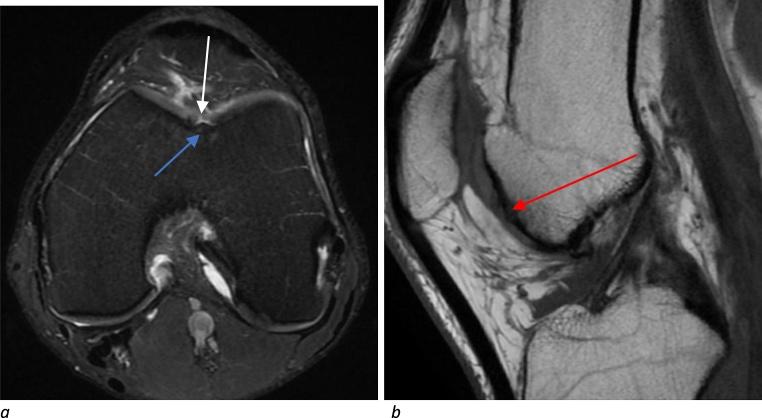

Knee MRIs obtained at the core imaging facility of the International Olympic Committee were blindly, retrospectively reviewed by a board-certified musculoskeletal radiologist for meniscal, ligamentous, and tendon abnormalities. Cartilage assessment was based on the modified Outerbridge criteria.

Of 122 athletes who received a knee MRI, 64 (52.4 %) had cartilage damage. Cartilage damage was more prevalent in the patellofemoral compartment (52 athletes, 42.6 %), followed by lateral (23 athletes, 18.9 %) and medial tibiofemoral compartments (12 athletes, 9.8 %). Patellofemoral cartilage damage was most prevalent in beach-volleyball (100 %), followed by volleyball (8 athletes, 66.7 %) and weightlifting (7 athletes, 70 %). Patellofemoral cartilage damage was most prevalent with quadriceps (8 athletes, 72.7 %) and patellar tendinosis (11 athletes, 61.1 %). Medial and lateral tibiofemoral cartilage damage was significantly associated with medial (8 athletes, 29.6 %) and lateral meniscal tears (16 athletes, 55.2 %), respectively. There was a trend for the percentage of athletes with cartilage damage to increase with age.

The majority of athletes at the 2016 Rio Summer Olympics who had a knee MRI showed cartilage damage. Patellofemoral compartment cartilage damage was most common and frequently observed in certain sports including volleyball, beach volleyball, and weightlifting. Overuse in these sports can contribute to patellofemoral cartilage damage and subsequent development of anterior knee pain. Cartilage damage was also observed with concomitant meniscal tears and older age.